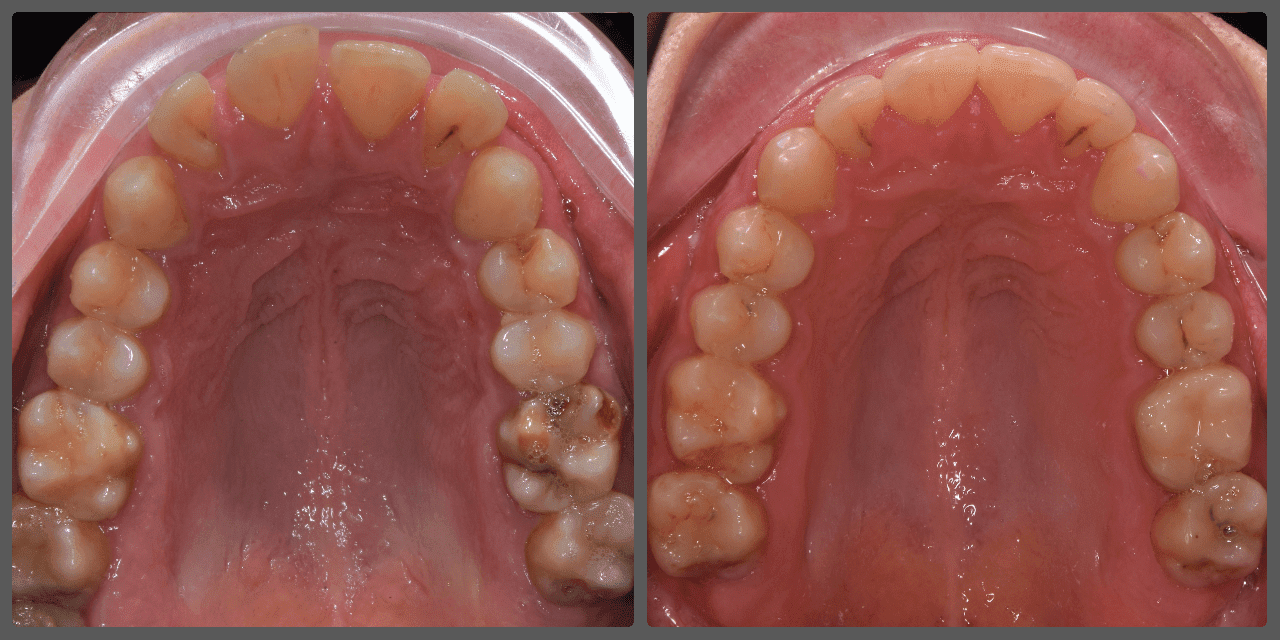

Balázs súlyos alsó torlódása miatt keresett fel magánrendelésemen. A diagnosztikus vizsgálatok során előbbin túl alsó-felső fogívszűkületet, valamint nyitott harapási hajlamot állapítottam meg. Kezelését Pitts21 alsó-felső rögzített fogszabályozó készülékkel kezdtük meg. A nyitott harapási hajlamot a hátsó fogakra helyezett harapásemelővel kontrolláltuk. A torlódott fogaknak tolórugóval és interproximális redukcióval teremtettünk helyet, és intermaxilláris gumihúzással tökéletesítettük a harapást. A fogszabályzó kezelés teljes időtartama alatt Balázs 110%-osan együttműködő volt, ezért 21 hónap alatt sikerült kiemelkedő végeredményt elérnünk.